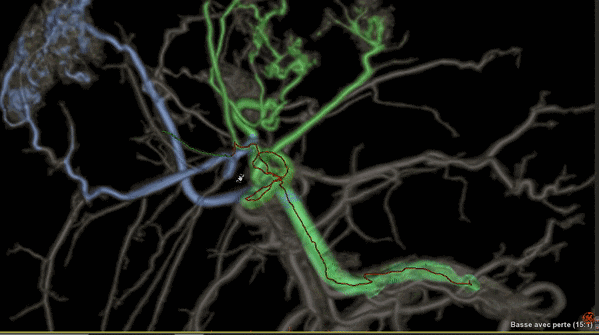

Liver ASSIST V.I,一種增強(qiáng)型軟件

可利用分析工具幫助臨床醫(yī)生克服腫瘤治療的挑戰(zhàn),例如,阻斷肝部腫瘤周邊供養(yǎng)血管是一種有效的介入治療方法,Liver ASSIST V.I可以通過(guò)精確高效的血管解剖分析來(lái)界定并精準(zhǔn)選擇注射點(diǎn),如同Google地圖一樣進(jìn)行路徑引導(dǎo),可以術(shù)前進(jìn)行手術(shù)預(yù)演來(lái)提供手術(shù)的精準(zhǔn)度,減少手術(shù)并發(fā)癥,讓人工智能的智慧在介入治療中閃光。